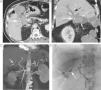

Paciente con HDB aguda masiva. A) La TC muestra una hemorragia activa de un divertículo del ángulo hepático del colon (flecha). B) La reconstrucción vascular permite demostrar el aporte vascular al divertículo sangrante (flechas) a través de una rama de la arteria cólica media. C) Arteriografía selectiva guiada por los hallazgos de la TC con embolización del vaso causante de la hemorragia.

A) TC en paciente con HDB masiva que muestra la extravasación de contraste en la cara ánterolateral izquierda del recto (flecha). B) La reconstrucción curva demuestra el origen de la hemorragia, procedente de la rama hipogástrica homolateral (flechas). C) La arteriografía se realizó de forma dirigida y centrada en el sector ilíaco, evitando el estudio inicial de la arteria mesentérica inferior y confirmando el origen, así como el sangrado activo (flecha); posteriormente se realizó la embolización selectiva (no mostrada).

Paciente con HBD masiva en el postoperatorio de una reconstrucción de Hartmann. A) Reconstrucción coronal de TC en fase arterial tardía que muestra una extensa extravasación de contraste en el colon izquierdo (flechas). B) La reconstrucción «volume rendering» delimita el origen vascular del sangrado en una rama de la arteria mesentérica inferior (flechas).

Paciente con sospecha de HDB masiva. A) El estudio de angioTC muestra un sangrado activo en el bulbo (flechas). B) La reconstrucción MIP delimita el origen del sangrado (flecha gruesa) a través de ramas de la arteria gastroduodenal (flechas finas). C) La arteriografía guiada por TC confirma la extravasación de contraste (flecha), con posterior embolización selectiva.